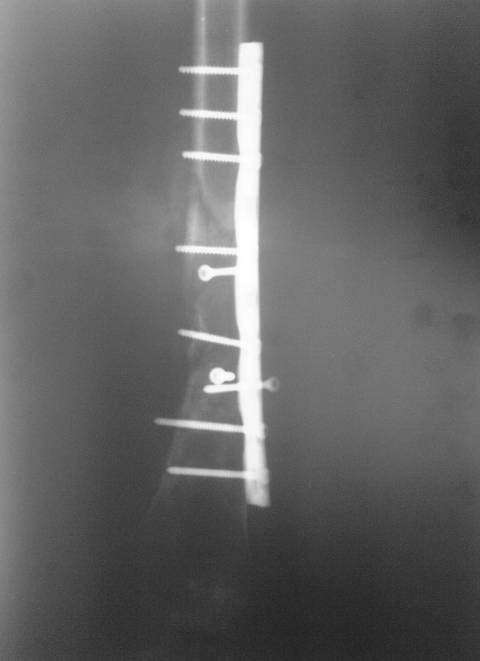

Травма в декабре 2006 года.Диагноз: Сочетанная травма. ЗЧМТ. Ушиб мозга. Кома.Закр. перелом левой плечевой кости; левой лучевой кости; оск. перелом левой бедренной кости.

Оперирована в январе 2007 года по выходе из комы и восстановления витальных функций. Накостный остеосинтез DCP-LC. Снимки прилагаются.

Через 4 месяца стали беспокоить боли и деформациябедра. На снимке угловая деформация AP - варус 11 град.; lateral - 29 град. Объем движений в коленном суставе: ограничение сгибания до 90 град. Локально - патологическая подвижность в нижней трети бедра. Локальная гипертермия, отек мягких тканей. Гиперемии нет. Передвигалась на костылях.

В мае 2007 года оперирована в Уральском НИИТО г. Екатеринбурга. Выполнено: полузакрытое удаление пластины и винтов, IM блокируемый остеосинтез.

На сегодняшний момент (2 месяца после операции). Больная передвигается при помощи трости из-за чувства неуверенности и ощущения онемения в подколенной ямке. В квартире передвигается без дополнительной опоры. Снимки в аттаче.

Вроде все на месте, и периостальные напластования были и до штифтования...